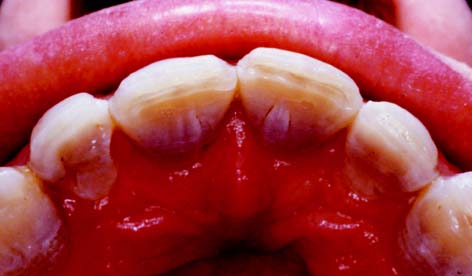

The complete ceramic crown is indicated in areas with a high esthetic requirement where a more conservative restoration would be inadequate (Fig. 11-3). Usually such a tooth has proximal and/or facial caries that can no longer be effectively restored with composite resin.

Fig. 11-3 A, Inadequately fitting all-ceramic crowns have led to recurrent caries and gingival recession around these central incisors. The patient was a professional model and therefore had exceptionally high esthetic requirements. B, The gingival defect was corrected by minor periodontal recontouring, the teeth were reprepared, and new all-ceramic crowns were provided.